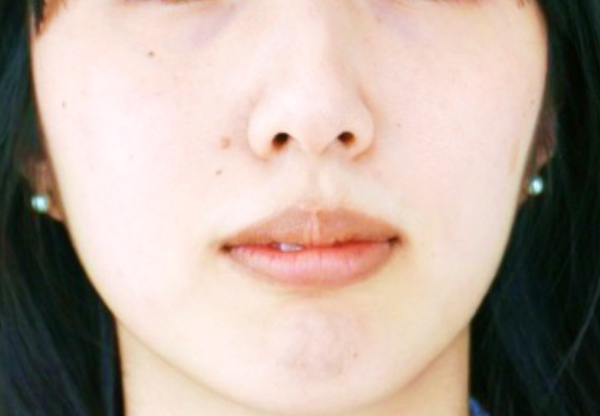

口元が突出したいわゆる“クチゴボ”状態を、

裏側(舌側)矯正で患者さんの期待を超えて治したい所を徹底的に治す治療。 -

【治療開始年齢】26歳

【治療費用】120万円(上のみ舌側装置)

【総治療期間】2年

【患者さんの症状】口元が突出したいわゆる“クチゴボ”状態で、下あごの先に梅干し状のしわがあり、締まりがなく、顔全体との調和のない口元となっています。上下ともにでこぼこも認められます。

【治療結果】知的で美しい口元となり、顔全体とのバランスも良く、社会でコミュニケーションを図る時に人と面と向かって接する重要な顔立ちを大きく改善することができました。QOL(生活の質)を挙げることができたと思います。治療が進んで顔立ちがきれいに変わっていくことで、診療室に入って来られても、最初の印象から誰だかすぐにわからないことがありました。そのくらいの改善を目指して治療に当たります。